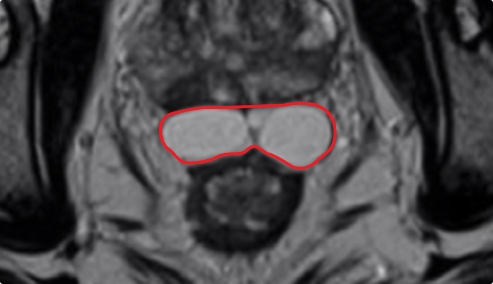

Control matters for improved symmetry.

Sculptable control over implant placement results in more symmetric coverage over the whole posterior rectal/prostate interface.

Implant Symmetry RESULTS6

>95%

Pivotal Trial Patients; % of implants centered on prostate midline